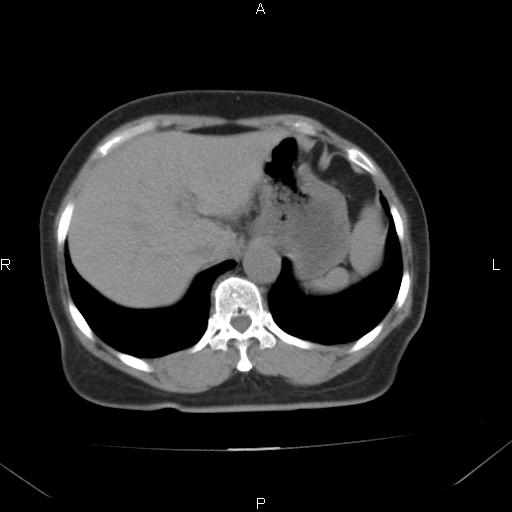

胸腺瘤

女、63Y 双眼睑下垂,早轻晚重。 胸腺瘤???

结果胸腺瘤